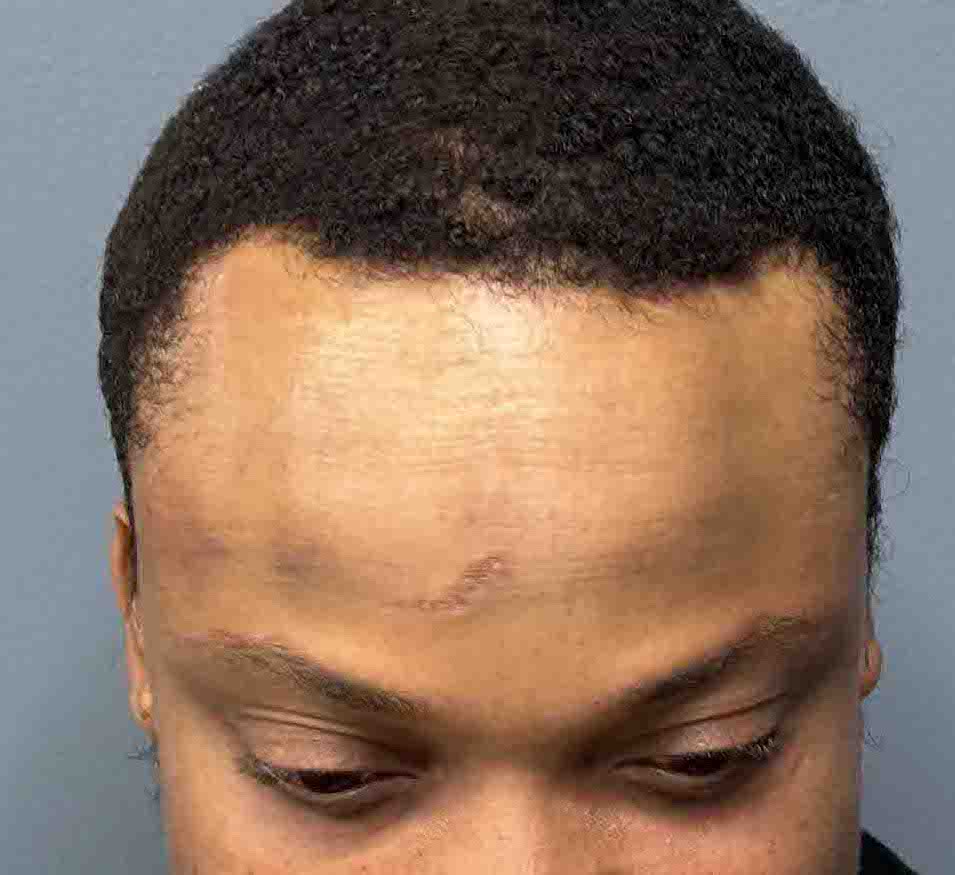

Patient 27

Desire for reduction of skull ridge reduction.

Anterior sagittal skull ridge reduction by bone burring.

Desire for reduction of skull ridge reduction.

Anterior sagittal skull ridge reduction by bone burring.